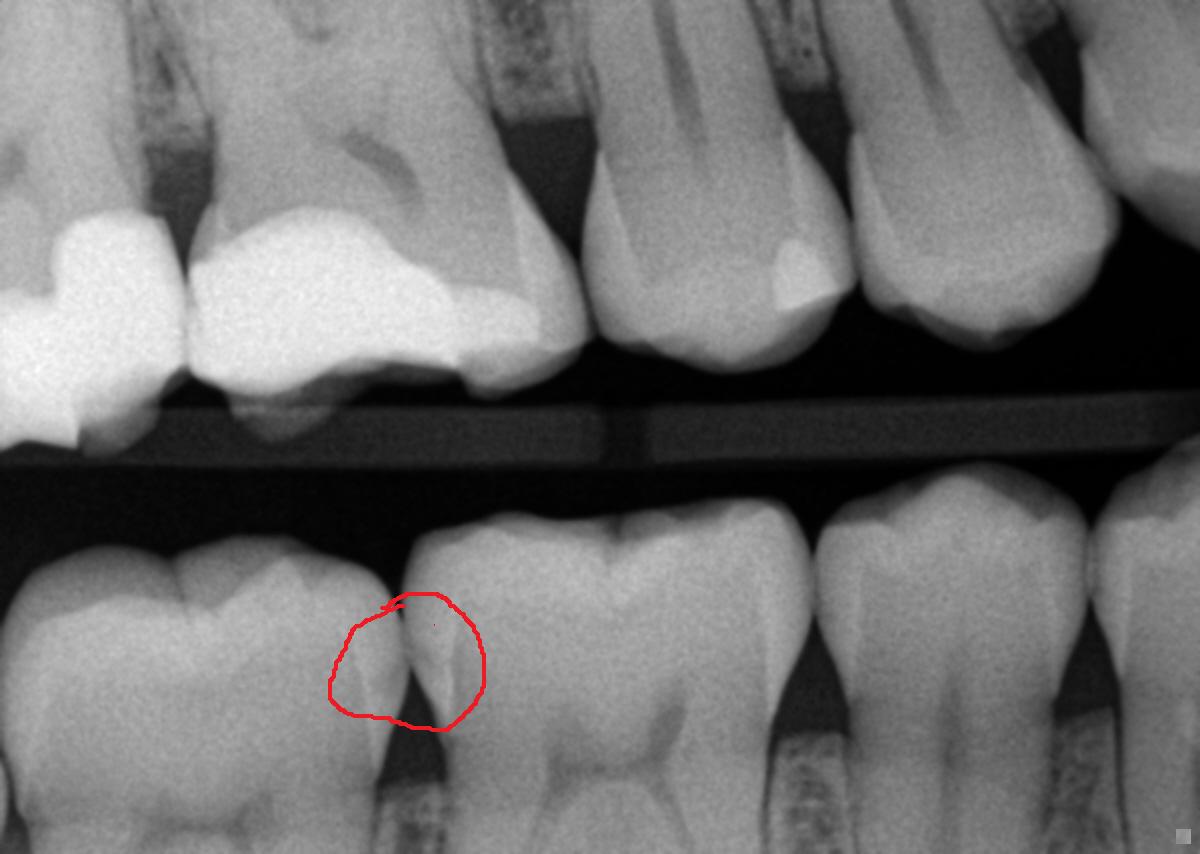

Obviously there is more scientific and dental verbage that can be used here, but that is the summary of what causes a cavity. Our mouths are dirty places and there are some nasty bugs in there. Some are known to cause cavities, others are known to cause gum and bone disease and some have been found to cause heart disease and/stroke (please refer to our previous blog entry about periodontal disease). The sugars and carbohydrates (chips, fries, bread, etc.) provide food for the bacteria and they also create a sticky matrix on the tooth that the bacteria can adhere. Most small cavities cause no symptoms. This is why you should see your dentist at least twice a year so we can detect these visually and radiographically. When you start noticing sweet or cold sensitivity, the cavitation is deeper in the tooth and the nerve is detecting those acids and temperature changes. The next step is the bacteria get so deep they enter the nerve chamber then it’s root canal time because the tooth hurts and the nerve within the root is now infected. So keep those preventative exam and hygiene appointments so we can catch those little cavities early. As you can see in the first x-ray, the dark area (aka the cavity) is shallow and the patient was having no symptoms. The second photo shows a cavity in the nerve and the patient said it was more painful than giving birth.